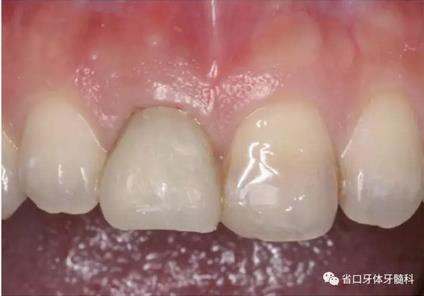

圖1 術(shù)前口內(nèi)照

圖2 術(shù)前口內(nèi)照

圖3 術(shù)前口內(nèi)照